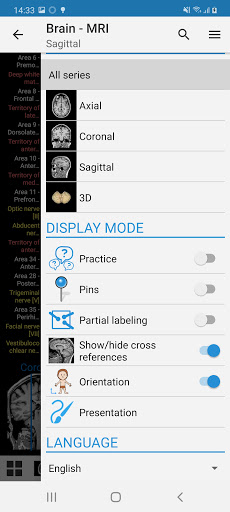

-إضافة الوضع المظلم.

- معلمة جديدة في قائمة المشغل لإخفاء النقاط التشريحية بدون تعليق.

- "التصفية حسب" ، في عرض التفاصيل ، يمكنك الآن تصفية الصور التي تحتوي على الهيكل التشريعي حسب الطريقة

- "التصفية حسب" ، في عرض التفاصيل ، يمكنك الآن تصفية الصور التي تحتوي على الهيكل التشريعي حسب الطريقة

-يمكنك الآن استخدام Facebook أو Google لتسجيل الدخول إلى التطبيق. -وضع الممارسة متاح الآن في اللوحة الجانبية أثناء عرض وحدة نمطية. (سيتم استبدال أسماء الهياكل بالأرقام ويمكنك النقر عليها لعرضها) - إعادة تسمية وتسميات جديدة للشرايين التاجية لوحدة تصوير الأوعية التاجية والأشعة المقطعية التاجية. أصبحت المصطلحات التشريحية أكثر تكيفًا مع التسميات الوعائية وممارسة التصوير القلبي. الخلل الصغيرة الثابتة